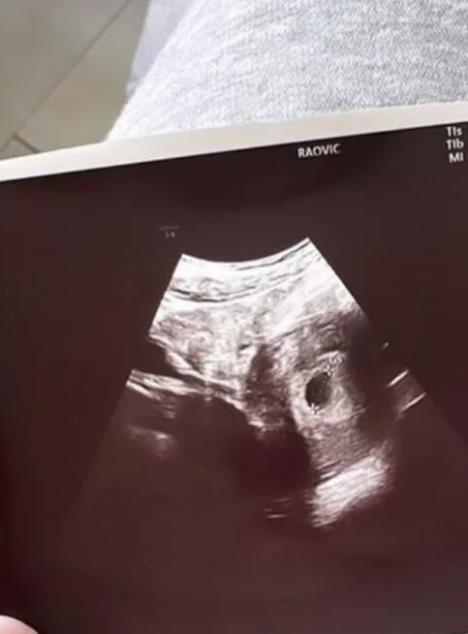

Podsetimo, starleta se oglasila putem društvene mreže Instagram i otkrila da je trudna. Prvo je podelila sliku pozitivnog testa za trudnoću, a zatim i svoje laboratorijske nalaze.

Deniz je sada potvrdila da je vest o njenoj trudnoći tačna ali i priznala da je i sama veoma zatečena ovakvim razvojem situacije.

- Imam samo jedan jajnik, nisam se čuvala, mislila sam da je nemoguće da zatrudnim. Nisam planirala trudnoću i baš me je zatekla ova vest. Kasnio mi je ciklus i danas sam uradila testove koji su potvrdili da očekujem bebu - rekla je Deniz.